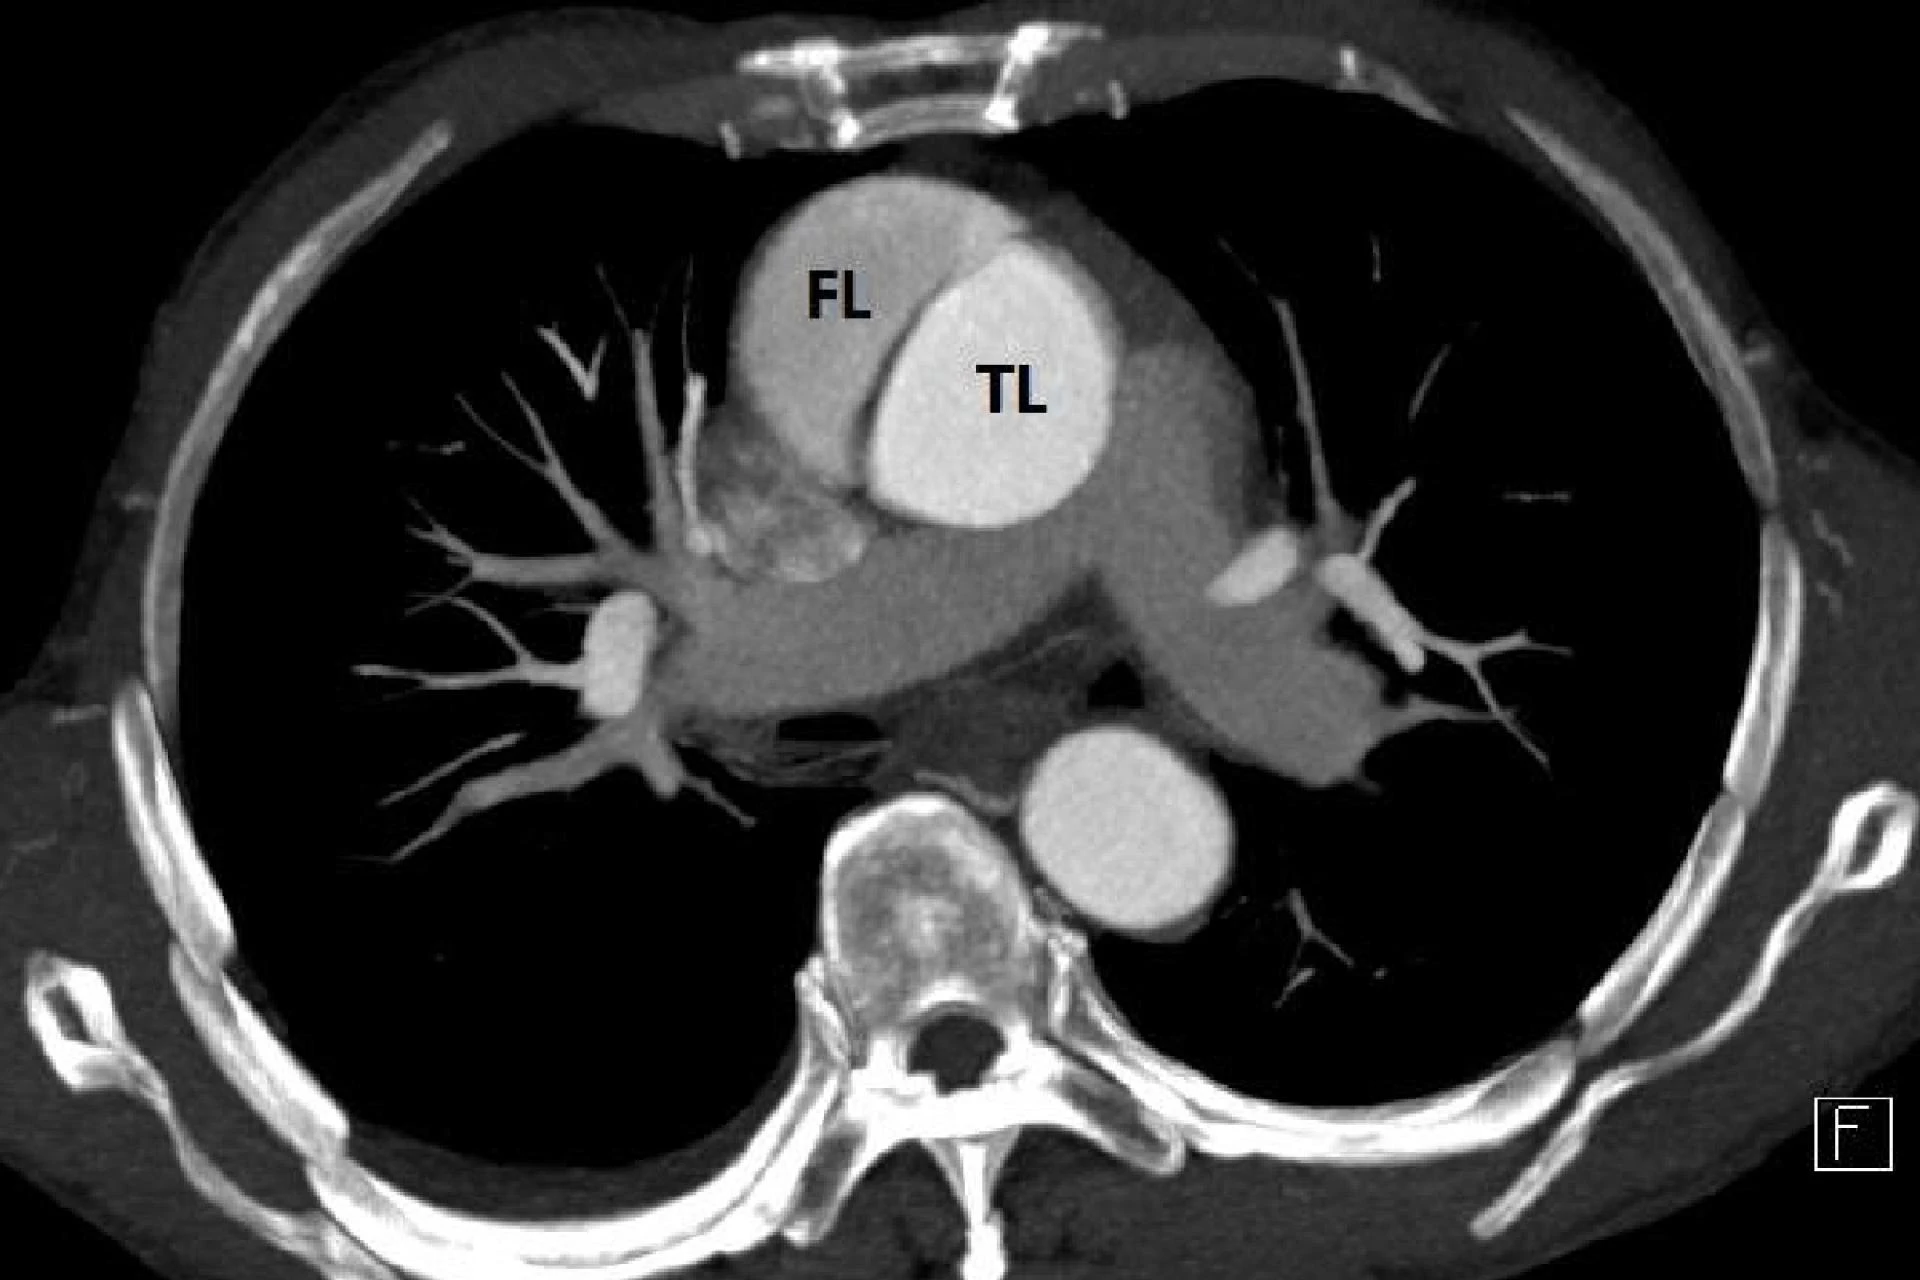

What Is Heart Surgery? A Brief Introduction

Heart Surgery Cost in Delhi, Best Cardiac Surgeon in India